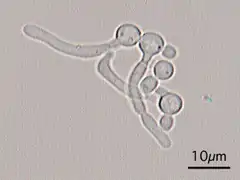

In its yeast form C. albicans ranges from 10 to 12 microns.[42] Spores can form on the pseudohyphae called chlamydospores which survive when put in unfavorable conditions such as dry or hot seasons.[43]

Although often referred to as dimorphic, C. albicans is, in fact, polyphenic (often also referred to as pleomorphic).[44] When cultured in standard yeast laboratory medium, C. albicans grows as ovoid "yeast" cells. However, mild environmental changes in temperature, CO2, nutrients and pH can result in a morphological shift to filamentous growth.[45][46] Filamentous cells share many similarities with yeast cells. Both cell types seem to play a specific, distinctive role in the survival and pathogenicity of C. albicans. Yeast cells seem to be better suited for the dissemination in the bloodstream while hyphal cells have been proposed as a virulence factor. Hyphal cells are invasive and speculated to be important for tissue penetration, colonization of organs and surviving plus escaping macrophages.[47][48][49] The transition from yeast to hyphal cells is termed to be one of the key factors in the virulence of C. albicans; however, it is not deemed necessary.[50] When C. albicans cells are grown in a medium that mimics the physiological environment of a human host, they grow as filamentous cells (both true hyphae and pseudohyphae). C. albicans can also form chlamydospores, the function of which remains unknown, but it is speculated they play a role in surviving harsh environments as they are most often formed under unfavorable conditions.[51]